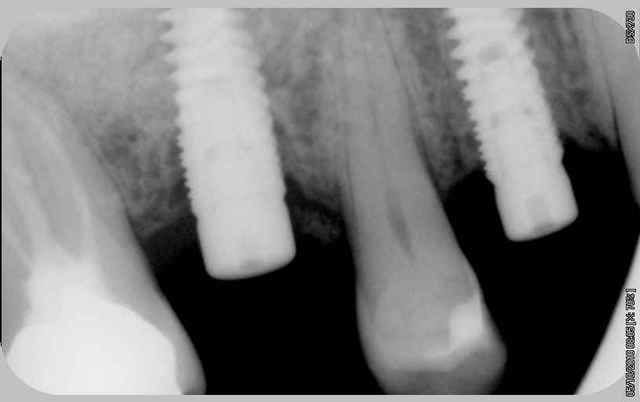

EII et Mise en vitrine immédiate, ici implant très enfoui, premier cliché à 3 mois post-op puis à un an (il faut préciser que le contrôle de plaque est plus que parfaitement réalisé par le patient).

(implant Dentium superline avec état de surface SLA)